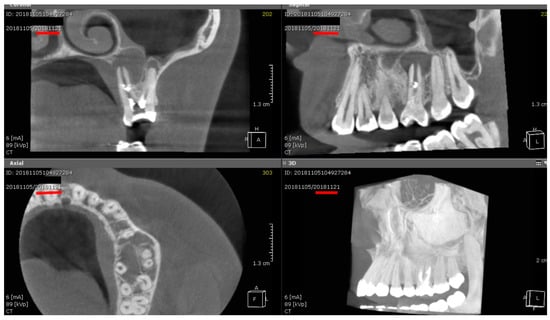

3.6. Representative Imaging and Healing Patterns